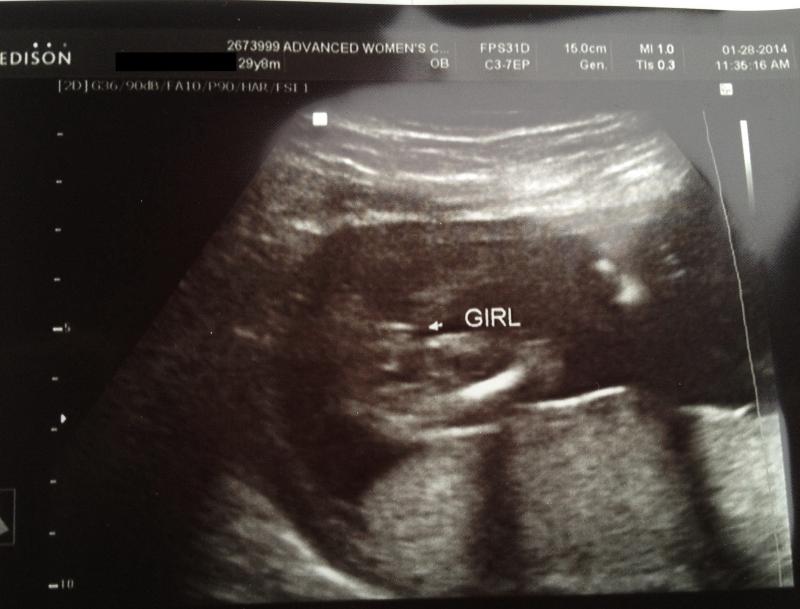

Then I had my anatomy scan on Tuesday (21w3d) and at first the baby was shy, keeping her (?) legs very close together. Then when she went to check again, they were more open and she said girl and pointed out 2 lines. After doing all the official stuff, she looked again a few minutes later and the legs were open a little wider and again, 2 or 3 lines were visible and definitely no boy parts or anything that could look like boy parts sticking out as she went back and forth. I know lines are what are looked for, but I thought it was typically 3 lines that you need to see to confirm girl? A friend of mine has me second guessing now since she said she thought 3 lines was girl and 2 lines was boy. The other thing that has me second guessing is the heart rate. I know it's an Old Wive's Tale and has been debunked by a study but the tech said that the majority of the babies she's seen have fit in with the theory of > 140 bpm being girl and under being boy. The HR was 124 bpm during the scan. (Though it's usally been around 144 or so on the doppler... my son's was also not in the theory though, his was usually around 150 or higher) Now I'm all confused because I'm obviously not a tech so I don't really know. A tech that is popular on BBC (Turtle) said she can't tell from the u/s pic so that made me even more worried...

Here is the print out of the "potty shot"

Attachment 16690